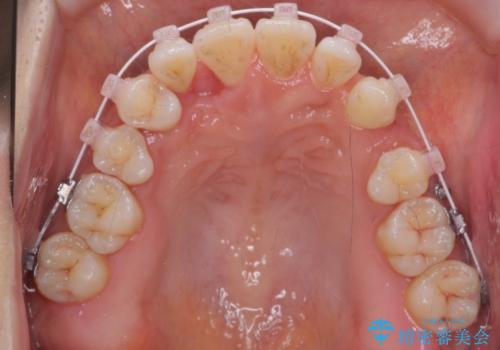

右上の半分埋まっている犬歯を抜歯し、残り上下左右3本抜歯してワイヤー矯正を行いました。

前歯が斜めになっているのもだいぶ改善しました。